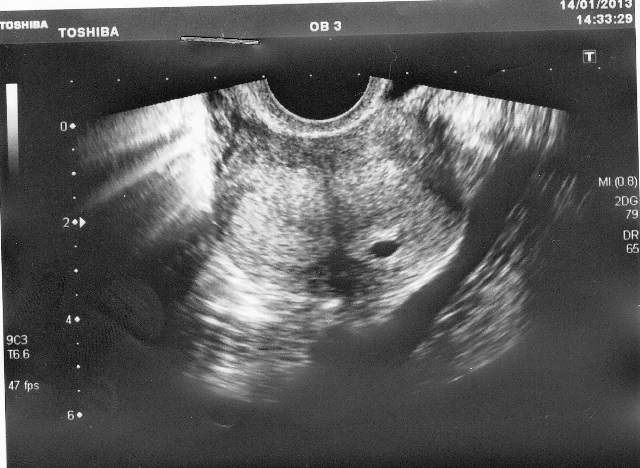

УЗИ

С трех недель развития эмбриона пациентку отправляют на ультразвуковое обследование. Более раннее проведение не желательно, если только есть подозрения на внематочную беременность. Во время исследования врач проверяет как прикрепился эмбрион, положение плодного яйца, полость матки, яичники. На мониторе видно количество эмбрионов, размер и соответствие сроку, насколько полноценно желтое тело.

Кроме того, данный анализ очень важен, чтобы определить, не развивается ли у женщины внематочная беременность или другие патологии, так как после ЭКО процент значительно выше по сравнению с естественным зачатием.